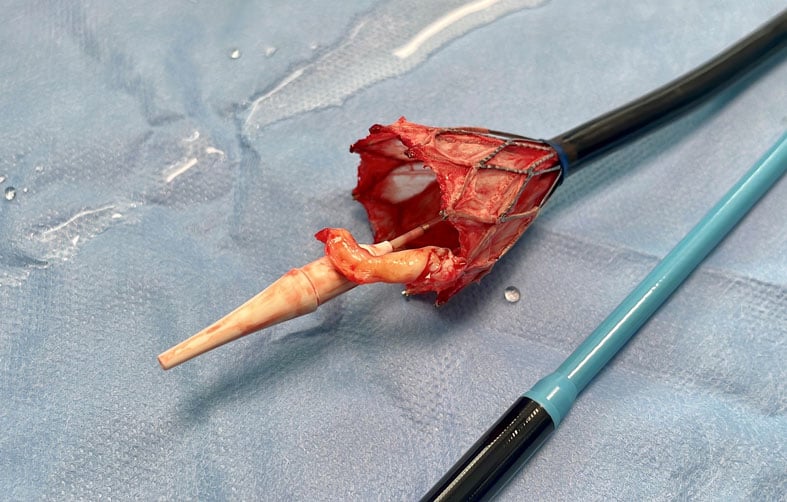

Leaflet avulsion due to resheathing during transcatheter aortic valve implantation bit.ly/4fscXw9 #EHJCaseReports Philipp Sommer Tee Joo YEO Aaysha Cader Boldizsar Kovacs Erik Rafflenbeul A.Nazmi Calik Obayda Azizy Sara Moscatelli EHJCaseReports Editor-in-Chief #CardioX

Caught in the act What do you see in this image? A: Large thrombus B: Large vegetation C: Part of an aortic leaflet Check if you got it right here ➡️ pcronline.com/Cases-resource… Submitted by Henryk Dreger, Iskandar Atmowihardjo and Sebastian Spethmann from 🇩🇪 and accepted for